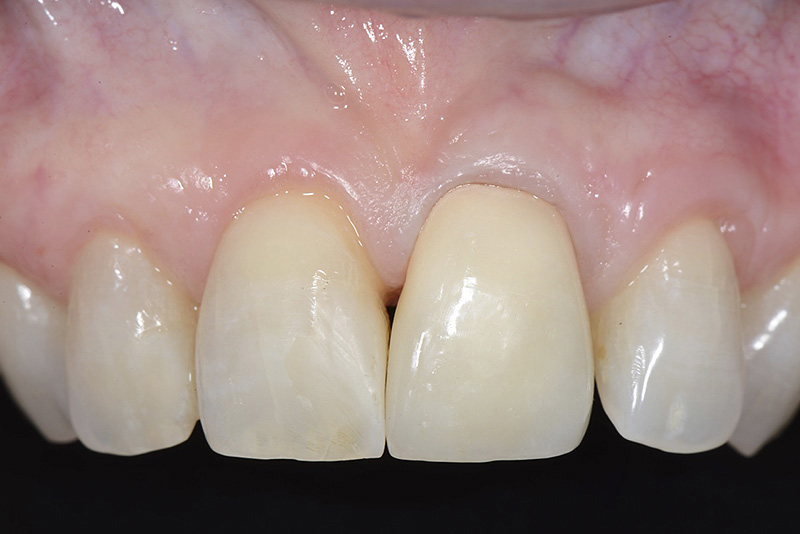

Vengono utilizzati 2 tipi di provvisori: il primo, cementato ai denti vicini, viene utilizzato dal momento dell’estrazione del dente fino ad impianto osteointegrato (circa 6 mesi); il secondo, avvitato direttamente all’impianto, ha una funzione di prova estetica ma soprattutto di guida per la maturazione dei tessuti gengivali peri-implantari portandoli verso la maturazione completa prima di posizionare la corona finale in disilicato di litio.